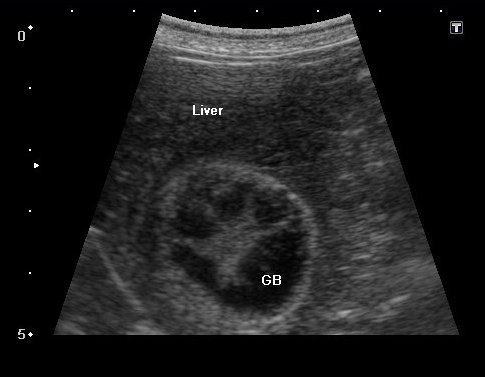

胆嚢粘液嚢腫の場合、エコー検査では放射状に胆泥が胆嚢壁に付着したキウイフルーツ状の所見が見られます。

エコーで胆嚢炎と胆嚢粘液嚢腫であることを確認し、破裂の危険性 を考えて腹腔鏡下胆嚢摘出術を実施することになりました。

臨床症状もなかったので腹腔鏡下胆嚢摘出術